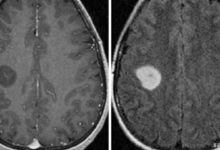

- Görüntüleme testleri: Görüntüleme testleri beyin tümörünün yerini ve boyutunu belirlemeye yardımcı olabilir. Bu testler ayrıca beyin omirilik sıvısı yollarındaki basıncı veya tıkanıklığı belirlemek için çok önemlidir.

Bilgisayarlı tomografi (BT) taraması veya manyetik rezonans görüntüleme (MRG) hemen yapılabilir. Bu testler genellikle beyin tümörlerini teşhis etmek için kullanılır. Perfüzyon MRG ve manyetik rezonans spektroskopi gibi gelişmiş teknikler de kullanılabilir.